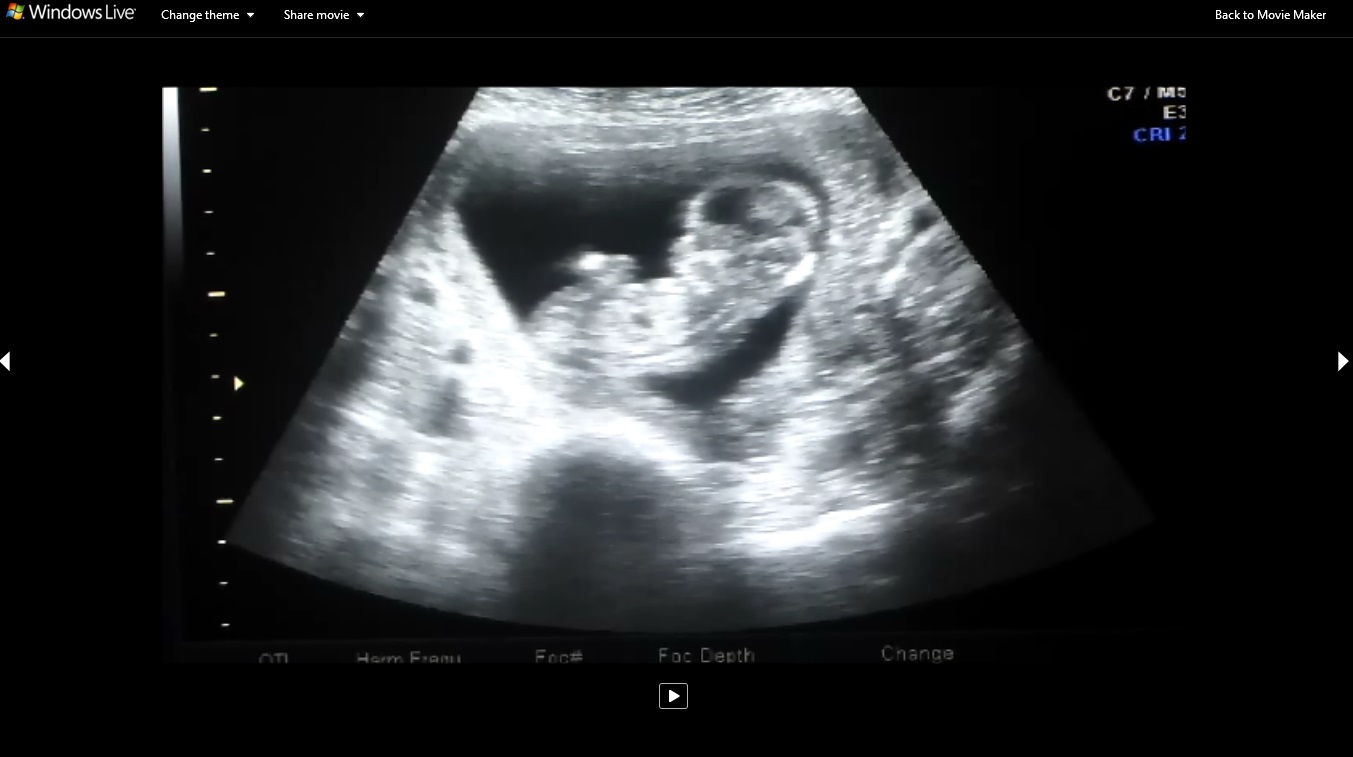

Second picture: Attachment 21435 Is that the nub???